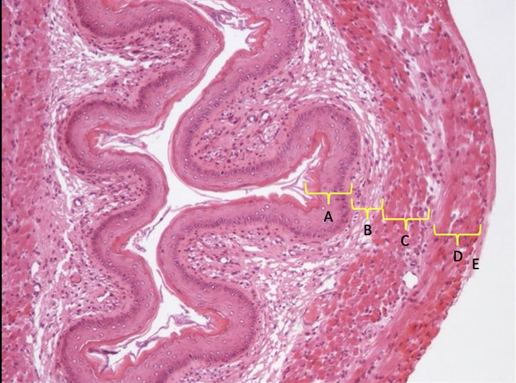

przydanka

błona mięśniowa: warstwa okrężna, mięśniowa, podłużna

blaszka właściwa

nabłonek przejściowy

moczowód nr 431

nabłonek przejściowy

blaszka właściwa (ewentualnie i mięśniowa)

a to tworzy błonę śluzową

błona podśluzowa

mięśniówka podłużna, okrężna i podłużna

przydanka lub błona surowicza w błonie śluzowej

brak gruczołów śluzowych

pęcherz moczowy nr 432